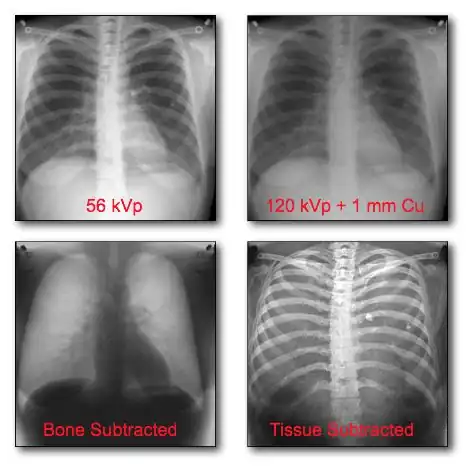

This form of image data processing is illustrated in the following figure:

A chest radiograph acquired at 56 kVp is shown in the top left panel of the figure. This is referred to as a low energy image. In the top right panel is a radiograph of the same patient's chest acquired at a high energy – 120 kVp, with 1 mm copper filtration. Results of the dual-energy processing are shown on the bottom row. The bone-subtracted image is shown in the bottom left panel and the tissue-subtracted image in the bottom right panel. Notice that the tissue-subtracted image demonstrates that the lesion in the patient's left lung is a calcified nodule, since it doesn't appear in the bone-subtracted image.